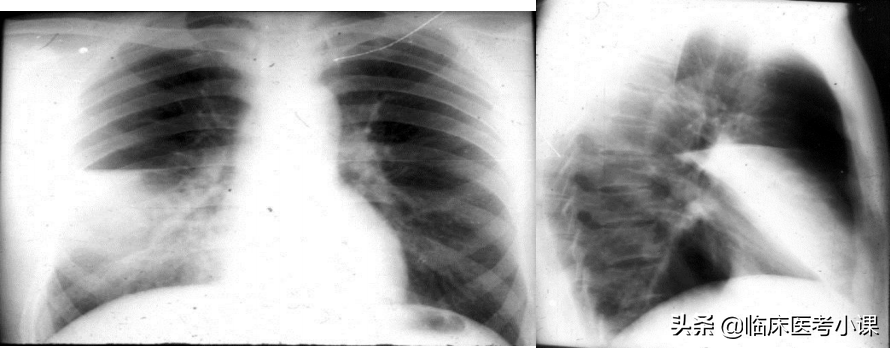

右前下胸第四肋以下闻及管呼吸音

患者左侧呼吸音消失,右侧呼吸音代偿性增强